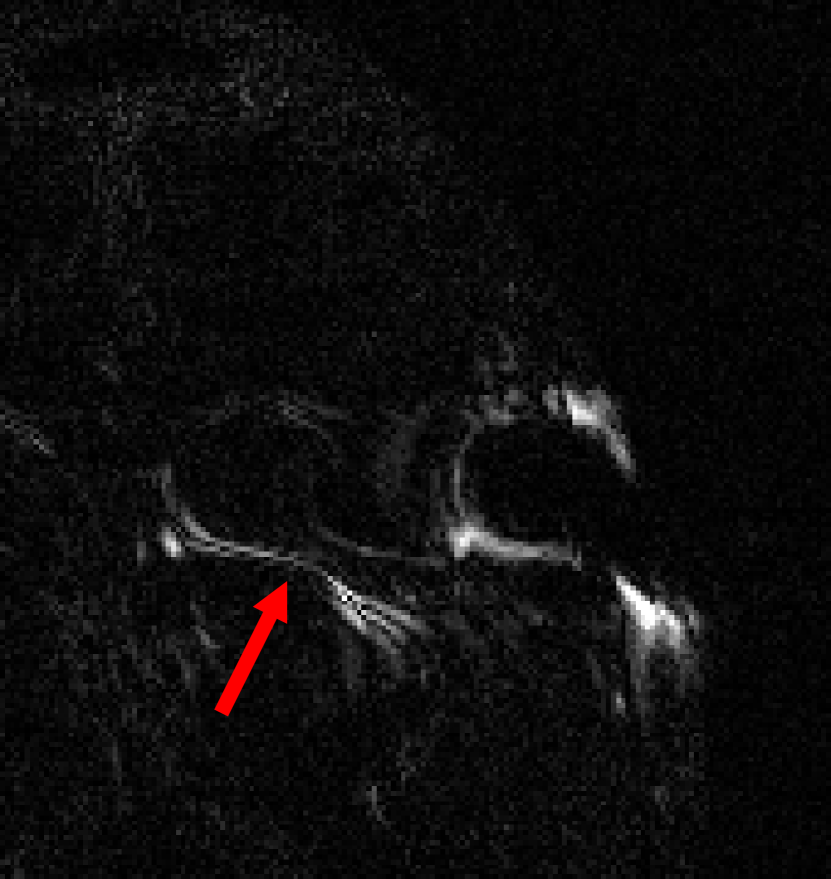

This result implies that random noise can also produce undesirable effects. In Fig. 3 we show several examples of this effect. For the first DL method, mean zero Gaussian noise causes the NN reconstruction map to hallucinate, by artificially removing an image feature (indicated by the red arrow). In the second case, certain image independent, small mean Gaussian noise causes severe instabilities in the recovered image. Notice that the noise causes the second DL method to exhibit completely nonphysical artefacts, which could be easily identified by a practitioner as a failure mode. Yet for the first method it creates seemingly realistic artefacts (hallucinations). Such pernicious artefacts may be impossible to detect.

A.3 Fig. 3

In the four leftmost images, we consider the DeepMRI-Net from [66]. This NN is composed of a cascade of U-Nets and data consistency layers. It has been trained on cardiac images, such as the one shown in the figure. The sampling operator is a subsampled two-dimensional Fourier transform, whose sampling pattern is shown in Fig. 7. The noise vector used in the experiment was created as , where is a zero-mean complex-valued Gaussian noise vector. Since the mean of a Gaussian random variable is unchanged by a linear transformation, the noise vector still has zero-mean.

The four rightmost images are from [7]. Code is available at https://github.com/vegarant/am_AI_hallucinating. Here we consider the AUTOMAP network from [82]. This NN was trained by the authors of [82] on brain images from the MGH–USC dataset [27]. It was trained using Fourier sampling with 60% subsampling. In [7], the perturbations

Here , and , are zero-mean Gaussian vectors. The vectors , , are worst-case noise vectors computed for an image that differs from the image used in the experiment. This makes the mean of the Gaussian noise vector image independent. The image used to compute the worst-case perturbations is shown in Fig. 6.